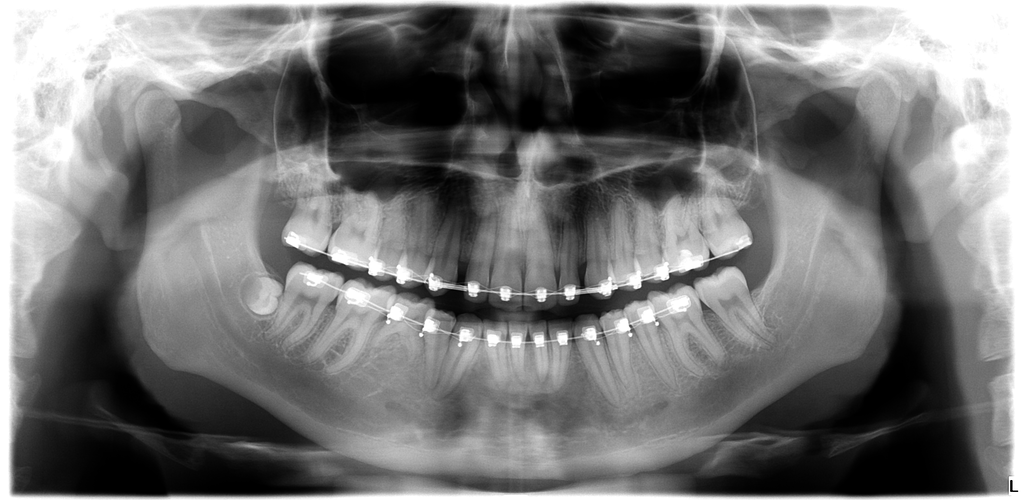

These are my CTs, how big do yall think i will ascend?

Before and after:

• Fabian_Noah_Luca_14012026_152010.png

Fabian_Noah_Luca_14012026_152010.png

2.5 MB · Views: 0